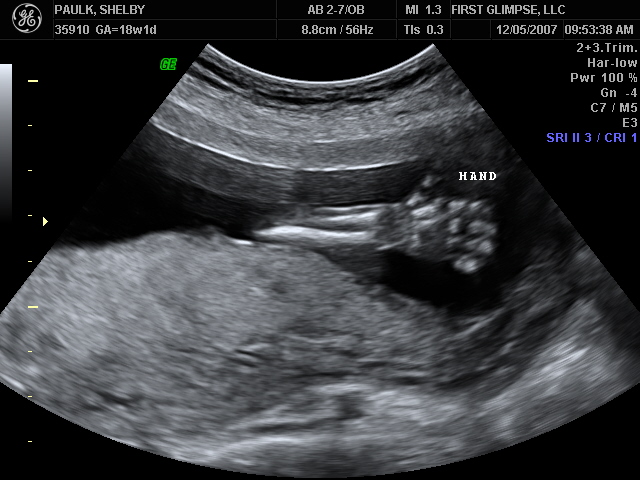

We had the ultrasound for baby number #2 on Tuesday, as we like to refer to HIM as (at least until we come up with a name, which could be a while given our track record). Yes, I said HIM…we are having a baby BOY!! We are so blessed to be have one of each. God is so good. Here are a few of the many ultrasound pictures that were taken. God has blessed us with one very healthy baby and we pray that this little guy is just as healthy. So far the docs. say everything looks great, we’ll have another ultrasound around 28 weeks because of where the placenta is located right now. It needs to move because it is blocking the cervix, but the ultrasound tech said that 9 of 1o times it will move…we pray that it does, because if it doesn’t I will have to have a C-Section.